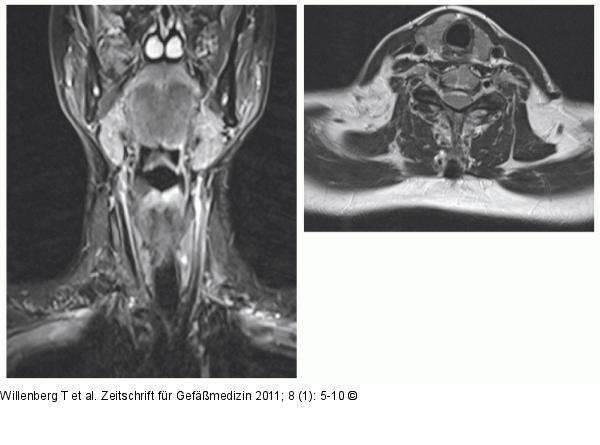

Abbildung 6: Kontrolle 3 Monate nach Sklerosierung Kontrolle 3 Monate nach Sklerosierung ohne Hinweis auf einen Rest- oder Rezidivbefund. |

Kontrolle 3 Monate nach Sklerosierung ohne Hinweis auf einen Rest- oder Rezidivbefund. |